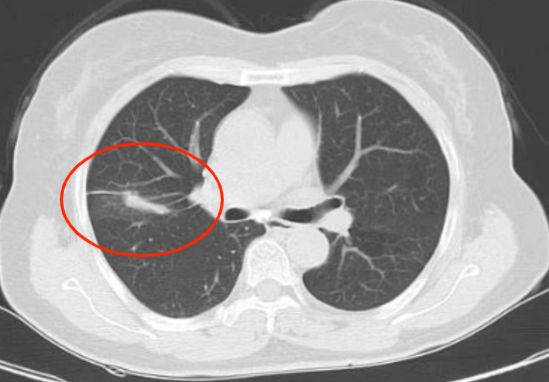

近年来,贵州航天医院各科室紧跟医学前沿,不断强技术、补短板,大力开展新技术、新项目,完成了许多高精尖、高难度、本地区“首例”的技术,填补了医院医疗技术空白,满足了群众日益增长的医疗需求。 贵州航天医院呼吸与危重症医学科是贵州省内呼吸疾病治疗规模最大,诊疗项目最全的呼吸疾病品牌科室,呼吸介入技术达到了全国先进水平,在贵州省内处于领先的地位。 本期,我们将为大家带来呼吸与危重症医学科特色技术——氩氦刀冷冻消融技术治疗肺癌、高危肺结节。 案例分享 患者在体检时发现右肺结节(10mm),就诊于当地我院一专科联盟合作医院,但因当地医疗条件有限,患者通过专科联盟绿色通道前往我院就诊,入院后,通过经皮肺穿刺活检,病理诊断为右肺原位腺癌,科室立即组织专家开展肺结节多学科会诊(MDT),为患者制定诊疗方案。 经充分的沟通下,患者及家属拒绝手术切除。科室再次严格讨论评估,患者情况满足氩氦刀冷冻消融术指征,再次将治疗方案与患者及家属沟通同意后,为患者制定并成功实施氩氦刀冷冻消融术。 冷冻消融术中 术后,患者定期复查,恢复效果良好。 术前 术后即刻 术后1月(反应性增大) 术后6月(纤维条索) 术后12月(纤维条索变细) 什么是氩氦刀冷冻消融技术 氩氦刀冷冻消融技术是一种先进的微创超低温冷冻消融肿瘤的医疗技术,它利用氩气和氦气的快速温度变化特性,实现对病变组织的精准冷冻和复温,以达到消融和破坏肿瘤细胞的目的。 氩氦刀冷冻消融技术原理 氩氦刀冷冻消融技术基于焦耳-汤姆逊效应,通过氩气和氦气的快速交换实现局部组织的超低温冷冻(-140℃到-190℃)和快速复温(20℃到45℃),当氩气通过金属杆尖端的蒸发器时,其气压突然降低,会大量吸收周围的热量,使金属杆尖部的气温迅速下降到超低温;随后,氦气在极短的时间内使组织迅速复温,通过热胀冷缩的原理,使肿瘤细胞爆裂。 (一)直接杀伤( 靶区冷冻消融效应) 1.快速冷冻(降温段):细胞内冰晶快速生长并撕裂细胞,导致细胞损坏。 2.慢速冷冻(低温段):细胞外冰晶生长导致水渗出细胞,造成细胞脱水。 3.升温:水迅速进入细胞,导致细胞涨破。 (二)间接杀伤( 冷冻的血管栓塞效应) 病灶区域快速冷热交替,引起微血管细胞脱水、蛋白质变性、微血管损伤、 冰晶及微血栓在微血管内形成,导致血小板聚集、血管栓塞, 局部细胞缺血坏死。 (三)抗肿瘤免疫( 冷冻免疫激活效应) 随着肿瘤细胞的破裂和坏死,促使肿瘤免疫调节因子停止分泌,逆转免疫抑制状态;可调控表面抗原,促进淋巴细胞增殖,提高身体抗肿瘤免疫能力。 氩氦刀冷冻消融技术优势 (一)精准度高:通过精确的靶点定位和温控技术,可实现对病变组织的精准冷冻和复温,避免损伤正常组织。 (二)微创治疗:对周围正常组织的热损伤小,无需开胸开腹,仅有一个针孔,恢复快,几乎无疤痕。 (三)适应症广:肺腺体前驱病变(癌前病变)、甲状腺结节、乳腺结节等;多原发磨玻璃肺结节,因各种原因不适合手术的早期肺癌、肝癌等;内科治疗无法控制的少发转移瘤等。 (四)可重复治疗:由于冷冻治疗对身体的创伤和痛苦较小,可以多次重复进行治疗,这对巨大的肿瘤和多发的肿瘤尤其适用。 (五)无毒性:冷冻治疗是以物理方法杀灭肿瘤,不向体内注射任何药物,避免外科手术、化放疗等对身体带来的巨大创伤和毒副作用,能有效减轻患者肿瘤负荷和痛苦,因此与化放疗、分子靶向药物等治疗方式相比属于无毒治疗。 氩氦刀冷冻消融技术对于早期肺癌、高危结节,可作为手术的替代治疗。对于晚期较大的肿瘤可作为姑息治疗,增强综合治疗的效果,可减少肿瘤负荷,减轻症状,提高生活质量,延长生存时间。 近年来,随着医学影像技术发展和肺癌筛查的广泛开展,肺内结节的检出率显著提高。无论肺内磨玻璃结节还是实性结节,单发或多发,都需要引起重视,定期复查,动态观察结节变化,如有需要请积极治疗。 贵州航天医院 呼吸与危重症医学科专家团队 廖江荣 国务院政府特殊津贴专家、遵义市呼吸疾病临床医学中心学科带头人、二级教授、主任医师 学术任职: 亚洲冷冻治疗学会副主席 第二届中国医药教育协会介入微创专业委员会呼吸分会副主任委员 中国抗癌协会肿瘤微创治疗专业委员会常务委员 中国防痨协会结核病转化医学专业分会常务委员 第一届中国人体健康科技促进会呼吸介入专委会常务委员 中国医疗保健国际交流促进会结核病学分会第三届委员会常务委员 中国抗癌协会肿瘤微创治疗专业委员会粒子治疗学组第四届委员会委员 中国结核病防治综合质量控制专家指导委员会委员 “西部呼吸介入联盟”副理事长 专业擅长: 呼吸系统(肺)疑难病的诊断及危重病的抢救,呼吸系统(肺)感染性、疑难性疾病介入快速诊断(ROSE),尤其在肺癌、肺小结节早期诊断,肺癌微创综合靶向治疗,难治性、复治性、重症肺结核诊疗,硬质支气管下复杂性气道狭窄诊治,纤支镜介入治疗气道肿瘤、结核、气道狭窄(球囊扩张、支架植入、高频电刀、氩气刀、冷冻、灌洗、注药、微波消融),间质性肺疾病的诊疗上具有极高水平;带领团队勇于创新,在贵州省率先开展多项新技术、新疗法,如CT引导下及纤支镜下I125粒子植入及CT引导下微波、冷冻消融介入治疗肺癌等多项新技术,带动了贵州省肺部疾病的介入治疗水平提高。 唐永江 四川大学华西医院 呼吸与危重症医学科 副主任医师 呼吸危重症医疗组长 香港中文大学博士 美国康奈尔大学访问学者 贵州航天医院 呼吸与危重症医学科 学科带头人 主要从事呼吸危重症(特别是呼吸重症感染)的临床及科研工作。 PCCM专培结业医师 中华医学会呼吸病学分会呼吸危重症学组秘书 中华医学会呼吸病学分会ECMO工作组成员 四川省医学会呼吸病学专委会介入学组委员兼秘书 发表文章20余篇,主持及参与多项国家自然科学基金及省卫健委基金。 蒋 婷 呼吸、感染党支部书记,呼吸与危重症医学科主任,副主任医师 专业擅长:从医20余年,在呼吸系统疾病、介入呼吸病学、肺部结核、肺部肿瘤等方面具有丰富的临床经验和专业技能,尤其是慢性阻塞性肺疾病、支气管扩张、肺结核、耐药肺结核、肺癌、胸腔积液等肺部疾病的诊治、微创介入、危重病患者抢救。 现任中国防痨协会人兽共患结核病专业分会委员,中国女医师协会第一届介入专业委员会委员,贵州省基层呼吸疾病防治联盟-间质性肺疾病联盟委员,贵州省防痨协会第七届理事会理事,贵州省中西医结合学会呼吸专业委员介入呼吸病学组委员,贵州省遵义市中医药学会中西医结合肺病(呼吸)分会副主任委员,贵州省遵义市中医药学会中医肿瘤专业委员会常委;发表论文数篇,参与并主持多项科研项目。 王 云 中共党员,呼吸与危重症医学科一病区副主任,副主任医师 专业擅长:擅长呼吸系统常见病及疑难危重症、介入呼吸病学、肺部肿瘤疾病的诊治,尤其擅长快速现场评价(ROSE)技术。 贵州省中西医结合学会呼吸专业委员会介入呼吸病学组委员,遵义市中医药学会中西医结合肺病(呼吸)分会委员,贵州省中西医结合学会第六届呼吸专业委员会委员。 李桂凤 中共党员,呼吸与危重症医学科三病区主任,副主任医师 专业擅长:从事呼吸系统疾病、结核病学、介入呼吸病学、肿瘤综合治疗、呼吸康复等临床工作20余年,擅长呼吸内科常见病、多发病及疑难重症危重病症的诊治,尤其对重症疑难结核及耐药结核病、介入治疗(肺)呼吸系统疾病、呼吸危重病抢救等方面具有较高诊疗水平。 中国防痨协会非结核病专业委员会委员,贵州省中西医结合学会第六届呼吸专业委员会委员,贵州省康复学会睡眠障碍康复专业委员会委员,遵义市呼吸内科医疗质量控制中心委员,遵义市落实民生实事结核病筛查阅片专家组成员;主持及参与实用新型专利3项。 周裕祥 中共党员,呼吸与危重症医学科四病区主任,副主任医师 专业擅长:经皮肺介入、经血管介入诊疗技术。 贵州省中西医结合学会呼吸专业委员会介入呼吸病学组常务委员,中国医师协会呼吸医师分会介入呼吸病学工作委员会呼吸病血管介入学组委员,贵州省中西医结合学会呼吸学分会委员,遵义市医学会放射肿瘤治疗学分会委员,中国医药教育协会介入微创呼吸分会委员,北京健康促进会中青年专家委员会胸部疾病精准活检分委会委员;曾赴重庆医科大学RICU、珠海市人民医院介入科进修学习。 杨 芳 中共党员,呼吸与危重症医学科内镜中心主任,副主任医师 专业擅长:从事临床工作约20年,对呼吸危重病的救治有独到的见解,尤其擅长呼吸系统疾病的介入诊疗,对呼吸内镜下的诊治及经皮肺穿刺诊疗技术具有丰富的临床经验。 亚洲冷冻治疗学会委员,中国医药教育协会介入微创呼吸分会委员,西南结核病医院联盟第二届委员会秘书/委员,贵州省中西医结合学会第六届呼吸科专业委员会委员,贵州省中西医结合学会呼吸专业委员会介入呼吸病学组秘书,贵州省中西医结合学会呼吸专业委员会基层康复学组副组长,贵州水利电力医学科学技术会高原医学分会委员,遵义市中医院学会中西医结合肺病(呼吸)分会秘书/常务委员,遵义市医学会肿瘤学分会(第二届)委员,遵义市医学会放射肿瘤治疗学分会第二届委员;主持及参与科研课题多项,参编著作《呼吸内镜操作技术规范》、《介入结核病学》,发表论文数篇。 贵州航天医院 呼吸与危重症医学科简介 贵州航天医院呼吸与危重症医学科以呼吸危重症和介入呼吸病学为强力推手,以肺部感染性疾病及肺癌、肺小结节的早期精准诊疗、慢性呼吸疾病康复治疗为特色,以人才团队建设为核心的科室发展模式,现已成为贵州省内呼吸疾病治疗规模最大、诊疗项目最全的呼吸疾病品牌科室。是贵州省医学重点学科、临床医学重点专科建设单位,遵义市首批呼吸重点学科、重点专科建设单位。是国家卫健委能力建设和继续教育肿瘤微创介入建设中心、贵州省县级医院微创介入培训中心、遵义市呼吸疾病临床医学中心。是国家呼吸医疗质量控制与管理哨点医院、遵义市呼吸内科专业医疗质量控制中心。是中国医药教育协会介入微创呼吸分会呼吸介入技术培训中心单位;国家卫健委海医会呼吸分会ROSE专委会“诊断性介入肺脏病学快速现场评价”培训基地;中国肺癌防治联盟“贵州航天医院肺结节诊治”分中心,中国人体健康科技促进会呼吸介入技术培训基地,贵州省中西医结合会呼吸学分会呼吸介入专委会主委单位。 基本情况 平均每年开展气管镜诊疗约4000例,经皮肺穿刺介入诊疗近千例,开展的项目包括经支气管镜(软、硬)下冷冻、氩气刀、高频电刀、球囊扩张、支架置入、超声内镜诊疗等气道介入诊疗技术,经皮肺穿刺活检及肿瘤消融术(微波、冷冻)、ROSE技术、内科胸腔镜诊疗及经血管介入诊疗技术,且多项呼吸介入诊疗技术在省内处于领先水平。 诊疗范围 专科擅长:致力于呼吸系统感染性、疑难性疾病的介入快速精准诊疗;肺癌与肺小结节早期精准诊疗水平项目提升。擅长呼吸系统(肺)疑难病的诊断及危重病的救治,尤其是肺癌、肺小结节的早期诊断,肺癌综合靶向治疗,肺结核综合诊疗等肺部疾病的介入诊疗在贵州省内处于前沿水平。 肺结节MDT门诊 贵州航天医院呼吸与危重症医学科微创介入诊疗技术已达到国内前列,省内领先水平,是亚洲冷冻治疗学会常务理事单位,并获批成立遵义市肺结节多学科(MDT)微创诊疗中心。 出诊信息 出诊时间: 周一至周五 8:00--12:00;14:00--17:00 出诊地点: 遵义市肺结节多学科微创诊疗中心(MDT)门诊(贵州航天医院呼吸综合楼1楼) 呼吸与危重症医学科与心胸外科、医学影像科、麻醉科等科室建立了多学科(MDT)会诊机制,结合患者情况,通过采取外科手术、冷、热消融等多种治疗手段,帮助患者安全、有效、精准、科学、快速治疗肺结节,单次消融手术时间约半小时左右,几乎没有疼痛,且并发症少,3-5天即可出院,有效减少了患者因开刀手术需长时间恢复的痛苦。 一审一校:周裕祥、黄成成